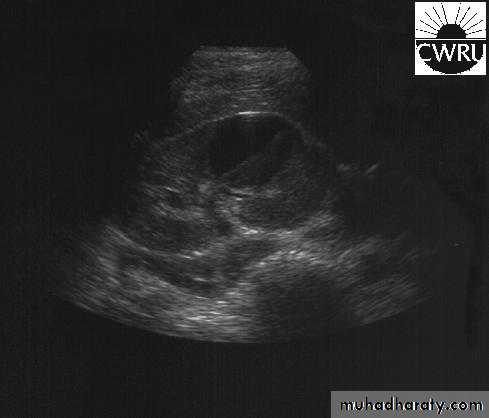

U/S: pus collection around the kidney with or without hydronephrosis.

U/S: cystic cortical lesion with internal echoes.

U/S cystic lesion with internal echoes (renal abscess)